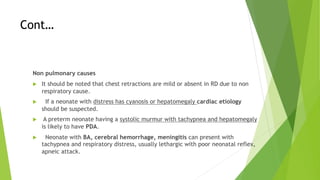

This document discusses respiratory distress and respiratory distress syndrome in neonates. It defines respiratory distress and describes the clinical signs. Various pulmonary and non-pulmonary causes are outlined. Respiratory distress syndrome, also known as hyaline membrane disease, is described in detail, including risk factors, pathophysiology, clinical presentation, investigations, complications, prevention, and treatment approaches like surfactant administration and nasal continuous positive airway pressure. The prognosis depends on gestational age and quality of care provided.